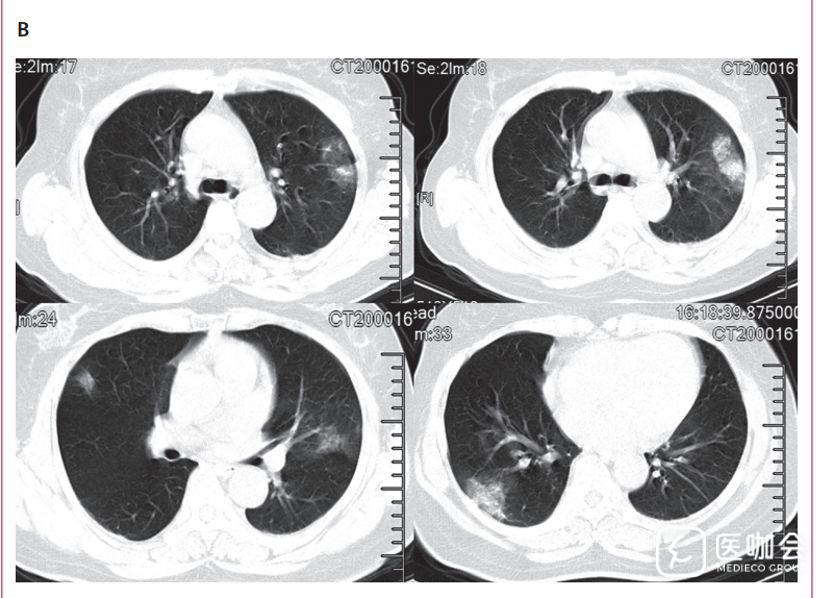

下图3是胸部CT的结果,分为ABC三张图。

C是在症状开始12天时,一位年龄53岁的女性胸部横面CT显示双侧磨玻璃状样变。